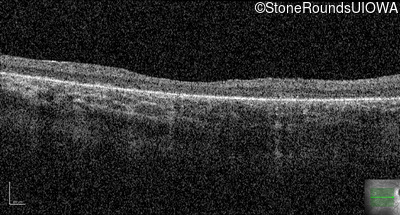

Age at visit: 10 years

OD OS

Age at visit: 11 years

Age at visit: 12 years

Age at visit: 13 years

Age at visit: 14 years

Age at visit: 16 years